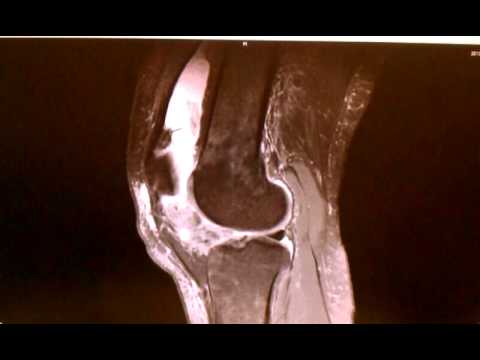

Mri 5 PVNS Pigmented Villonodal Synovitis :

Pigmented Villonodular Synovitis (PVNS) :

PVNS and SOC Proliferative Diseases of the Synovium :